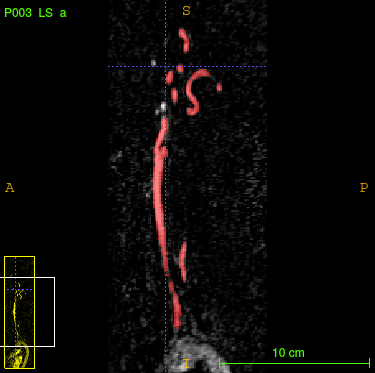

As one targeted application, we test the proposed model for segmenting blood vessels in 3D magnetic resonance angiography (MRA) scans (Fig. 1). We are given volumetric MRA scans of 119 patients provided by the Department of Neuroradiology Innsbruck 111https://www.i-med.ac.at/neuroradiologie, which face the arteries and veins between the brain and the chest. Also the 3D ground truths of these 119 patients have been provided. These segmentation masks have been generated by hand which takes hours for each patient. Our goal is the fully automated generation of sparse 3D segmentation masks of those vessels. For that purpose we use deep learning and neural networks. At the first glance, this problem may seem to be quite easy because we only have two labels (background and blood vessel), where thresholding could be applied. However, we are not interested into segmentation of those vessels with highest intensity, but in those which assist the doctor to detect dangerous to health abnormalities. This is the reason why we can not use sliding-window techniques, since the model is not able to determine out of a small patch if the seen vessel is “important” for the segmentation. Other challenges are caused by the big size of the volumes ( voxels) and by the very unbalanced distribution (in average, 99.76 % of all voxels indicate background).

As mentioned in the introduction, the main idea is to include projection layers from different directions. Due to the high sparsity and the orientation of the vessels in our application, maximum intensity projection (MIP) as projection technique seems to be an appropriate choice (Fig. 2).

Although the 3D U-net demonstrates high precision in our sparse application (Fig. 4,4), it produces too much artefacts, which constitutes an essential drawback. Additionally, we are very limited in the choice of convolution layers and corresponding channel sizes due to the huge size of the input data. So with this model it is hardly possible to conduct end-to-end segmentation for even larger biomedical scans with more channels on our GPU.

As we observe in Fig. 4, the slice-by-slice approach even generates more artefacts. Also the high standard deviation of the metrics between different test samples shows, that this approach does not generate segmentations with consistent reliability, which is a huge drawback.

Considering evaluation metrics, the random approach outperforms all prior discussed models and the problem of artefacts vanishes (Fig. 4,4). Furthermore, it uses nearly the same memory space as the 3D convolution model during training, but is also applicable to bigger input scans without memory concern due to the 2D convolution part. This is not possible for the 3D U-net.